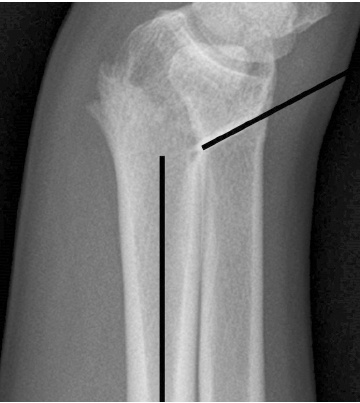

도수 정복 이후 측정한 원위 요골의 영상학적 인자들이 ‘허용 가능한 각도’의 범위일 경우에만 보존적 치료를 시작하였다. 요측 전위 정도는 손목의 전후방 X-ray 사진에서 원위 요골 골편의 요측 이동 정도를 의미한다(Fig. 1). 전후방 전위 정도는 손목의 측방 X-ray 사진에서 원위 요골 골편의 전후방 이동 정도를 의미한다(Fig. 2). 배측 피질골 파절 각도는 원위 요골 골편의 후방 피질골과 요골의 장축이 이루는 각도라고 정의하였다. 배측의 분쇄가 심한 경우에는 단순 방사선 영상에서 가장 뚜렷하게 관찰되는 후방 피질골을 기준으로 각도를 측정하였다(Fig. 3). 수배측 분쇄 골절은 측방 X-ray 사진에서 원위 요골의 수배측에 별개의 골절편(free-floating bony fragment)이 존재하는 경우로 정의하였다(Fig. 4).18) 모든 영상학적 인자들은 도수 정복 전의 초기 단순 방사선 사진 또는 컴퓨터 단층촬영 영상을 토대로 측정되었다. 본 연구는 본원 기관생명윤리위원회(Institutional Review Board, IRB)의 승인(IRB No. 2022-01-013)을 받아 시행한 연구로, IRB에 의해 환자 서면동의서 획득은 면제되었다.

Fig. 3

Dorsal cortical break angle is defined as the degree between the posterior cortex of the distal fragments and the long axis of the radial shaft.